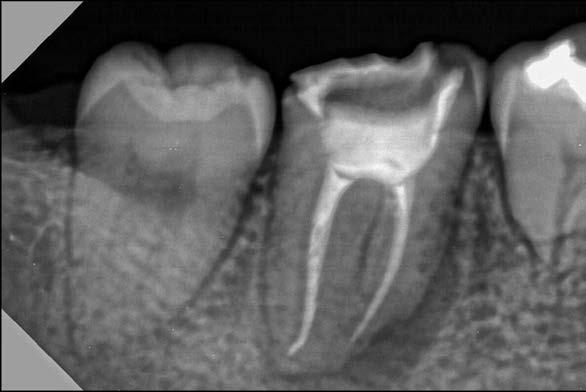

44 | CASO CLÍNICO

Autotrasplante de terceros molares mediante el uso de una guía de impresión tridimensional: Revisión de la literatura y reporte de un caso clínico